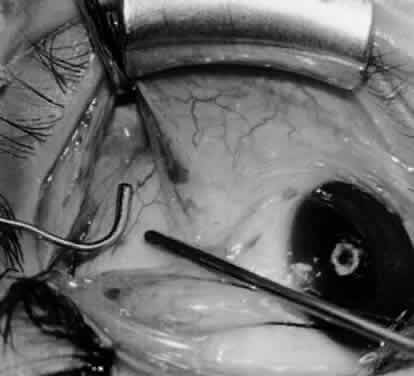

Fig. 14. The inferior temporal vortex vein, 8 mm posterior to the temporal insertion of the inferior rectus muscle, is held on a Green muscle hook.

Fig. 15. The placement of sutures within the sclera for a recession procedure of 10 mm. The anterior suture is placed 3 mm temporal and 2 mm posterior to the lateral insertion of the inferior rectus muscle, and the posterior suture is placed 3 mm further posteriorly.

Fig. 16. Two sutures straddle the inferior temporal vortex vein insertion for a 14-mm recession procedure.

Fig. 17. Knots are tied to show the placement. The inferior oblique muscle is held on a Stevens muscle hook.